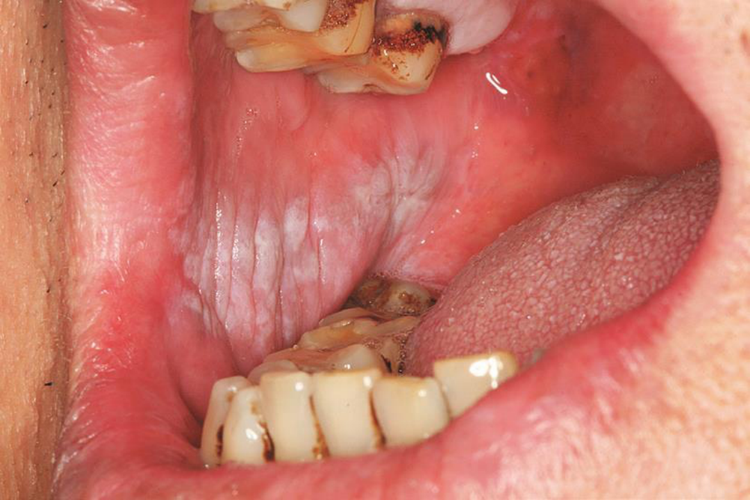

口腔白色角化病:位于颊部损害,以颊线区域为中心前后分布的白色斑片,表现为灰白色浅白或乳白色的边界不清的斑块或斑片,可连接成线状。皮损一般不高出于或微高于黏膜表面,平滑、柔软而无自觉症状,表面光滑无结节,基底柔软。

口腔白色角化症:主要由于口腔内残根、残冠、不良修复体或吸烟等常见的局部刺激因素导致口腔颊粘膜出现上皮过度角化或部分不全角化,出现口腔两侧黏膜变白,呈现条状斑片。